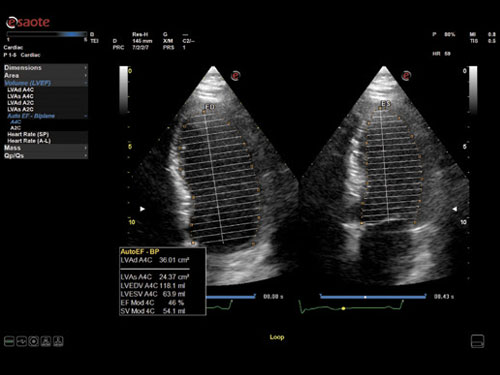

AutoEF: Automatické měření ejekční frakce (plně automatické).